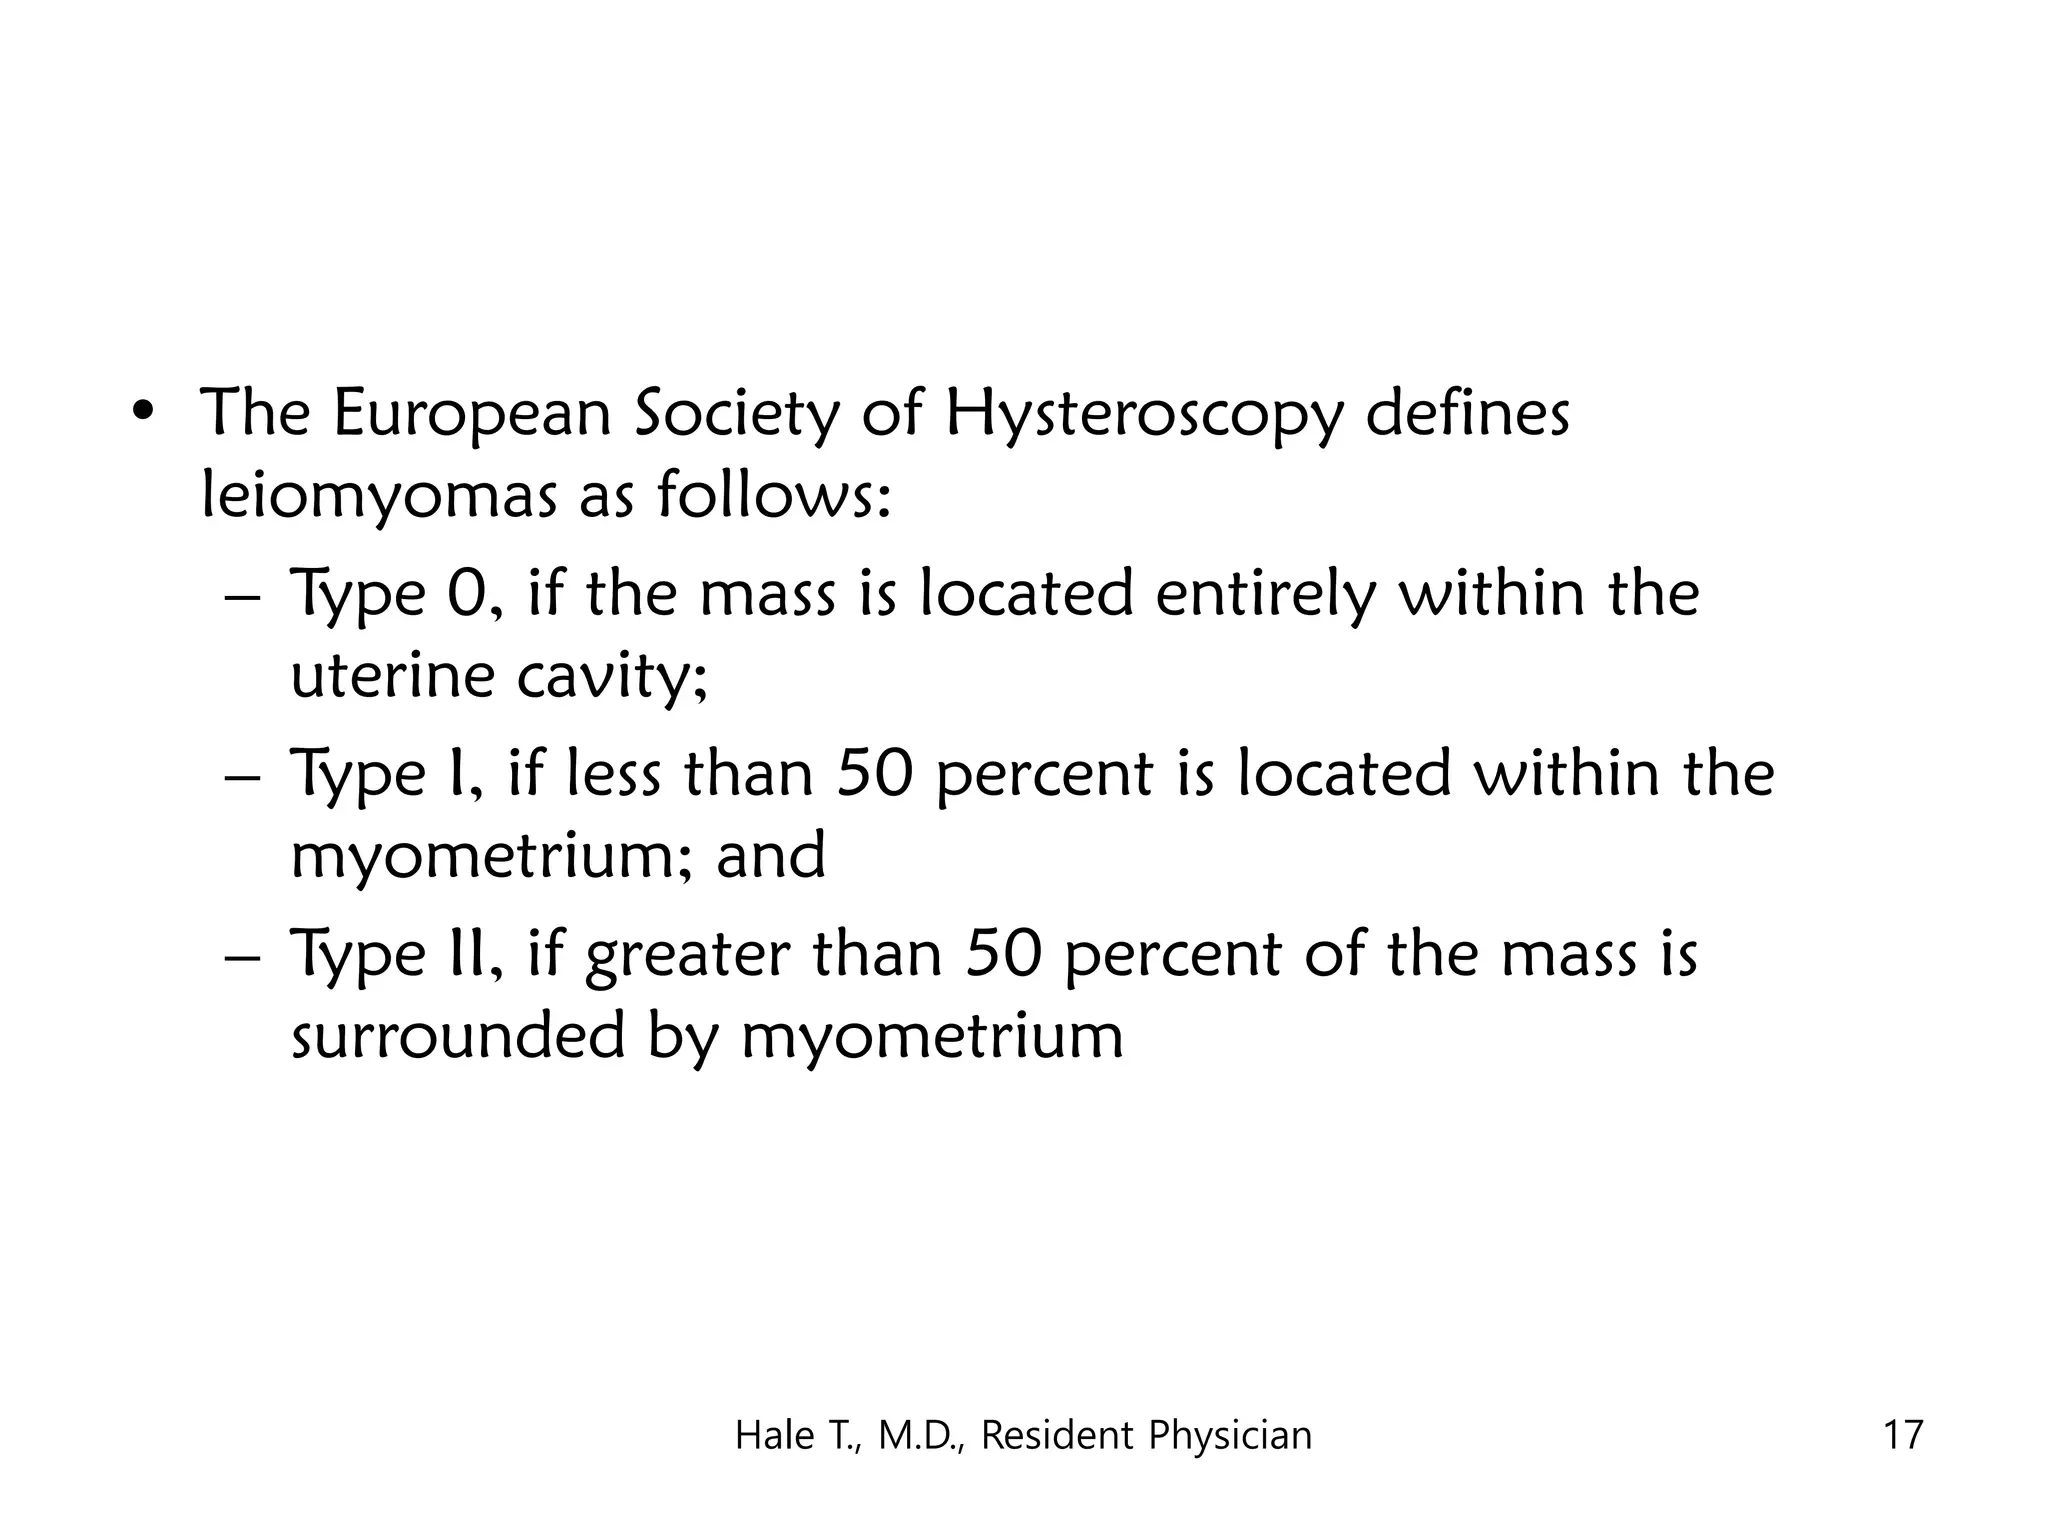

This document discusses myomas (uterine fibroids). It notes that myomas are benign smooth muscle tumors that originate in the uterus and are sensitive to estrogen and progesterone. Symptoms can include bleeding, pain, pressure, and infertility. Diagnosis is usually made through imaging like ultrasound or MRI. Treatment options include observation, drug therapy, uterine artery embolization, or surgical removal of the fibroids. The document also discusses complications that can arise if fibroids are present during pregnancy, such as pain, bleeding, preterm birth, and pregnancy loss.